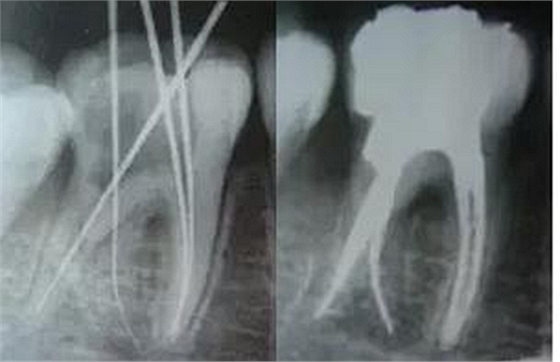

最后來(lái)玩一個(gè)根管治療質(zhì)量的評(píng)估——下圖是武大彭彬教授的一個(gè)病例,仔細(xì)觀察可以挑出一點(diǎn)問(wèn)題,但問(wèn)題事出有因!看看你的“眼力”如何——問(wèn)題在那里?教授的專業(yè)水平是不用懷疑的,那么事出的原因可能是什么?

問(wèn)題答案:這個(gè)病例的問(wèn)題主要反應(yīng)在開(kāi)髓的洞形修整,注意觀察該牙X-RAY的左側(cè)洞壁,如果常規(guī)情況制備成這樣是由于裂鉆破壞了洞壁和洞底所形成的臺(tái)階。如果評(píng)估根管治療的質(zhì)量那是要扣分的!但這個(gè)病例仔細(xì)觀察洞壁形態(tài)就可以看出:該病例屬于再治療的病例,因此還是屬于一個(gè)理想的病例。